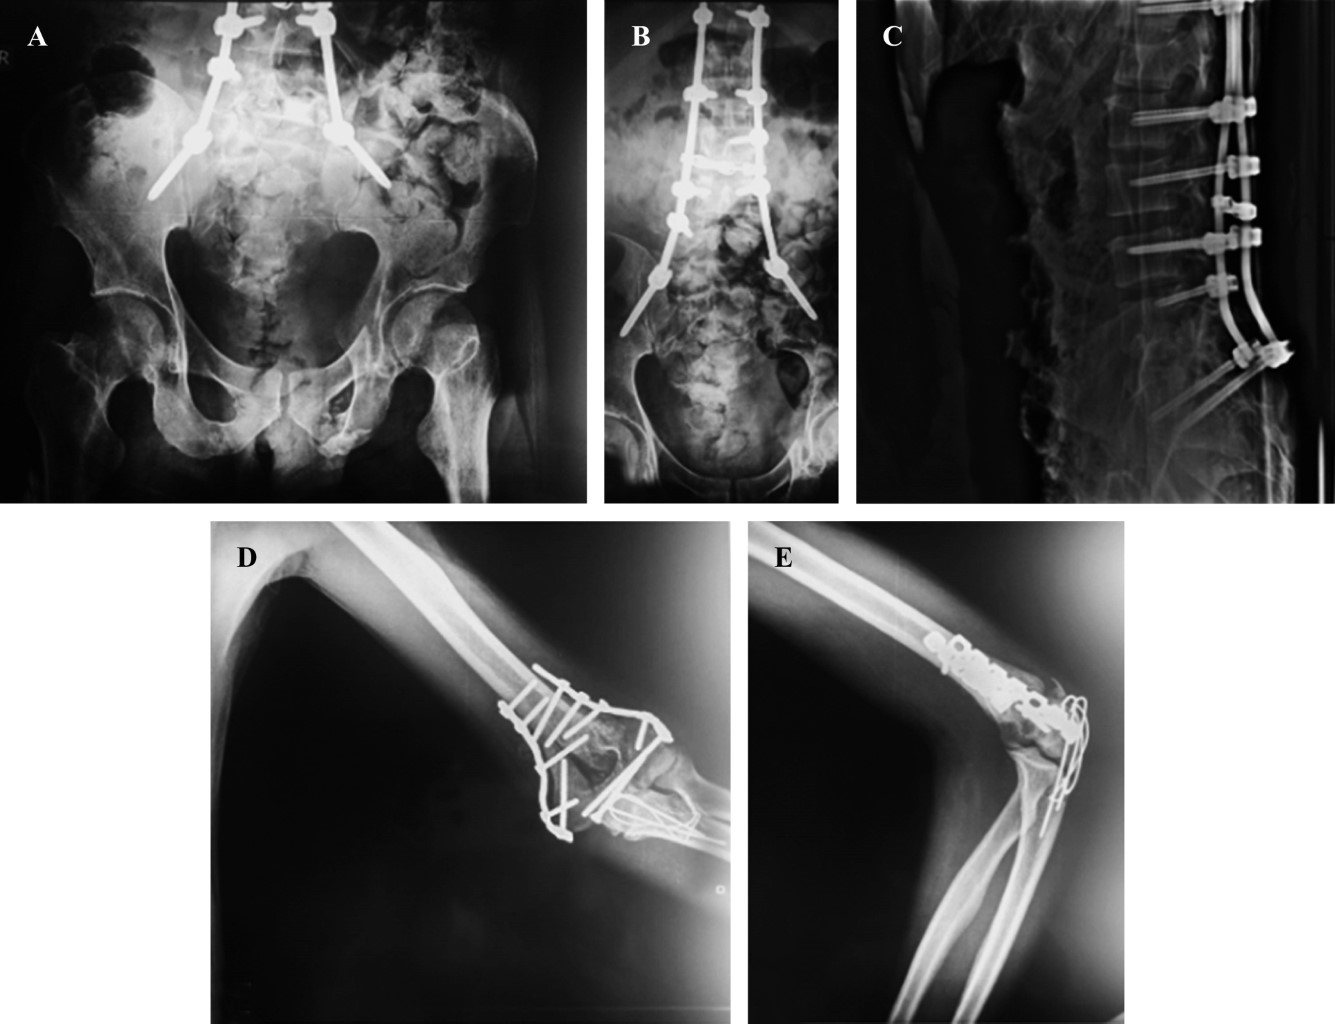

El paciente es estabilizado y se ingresa a la unidad de ortopedia para la realización de manejo quirúrgico definitivo. Se realiza para la columna y pelvis una planificación preoperatoria tridimensional con ayuda de realidad virtual (Figura 5), en donde se decide por la pérdida de capacidad de carga de la columna lumbar y su limitación de transmisión de cargas hacia la pelvis, realizar con un abordaje posterior en línea media de región de columna, una instrumentación posterior espinopélvica larga con colocación de tornillos transpediculares bilaterales en T12, L2 y L4; así como instrumentación de pedículo derecho en L5 y pedículo izquierdo en L3, además de instrumentación de ilíaco bilateral con tornillos en corredor LC2, con barras laterales y dando distracción entre T12 y L1 y entre L5 e ilíacos, se coloca además un crosslink para incrementar la rigidez del constructo de nuestra instrumentación espinopélvica larga. Además, se procede en el mismo tiempo quirúrgico una reducción abierta y directa con osteotomía del olécranon tipo Chevron y fijación interna del húmero distal bajo principio biomecánico de sostén con doble placa de reconstrucción en configuración medial y lateral con placas paralelas (Figura 6). En el postquirúrgico inmediato se realiza tomografía con supresión de metales y reconstrucción 3D para valorar adecuada posición de los tornillos transpediculares (Figura 7).

El paciente evoluciona sin infección y con cicatrización completa de las heridas sin sufrimiento cutáneo. El seguimiento del paciente a la actualidad muestra progresión en la consolidación de las fracturas del anillo pélvico y columna a los tres meses de evolución sin colapso de los cuerpos vertebrales ni cizallamiento del sacro sobre los ilíacos, el paciente recuperó la función de la marcha adecuadamente, con mejoría en la sensibilidad completa; se recomienda el retiro de implantes de la columna vertebral para lograr el máximo beneficio.